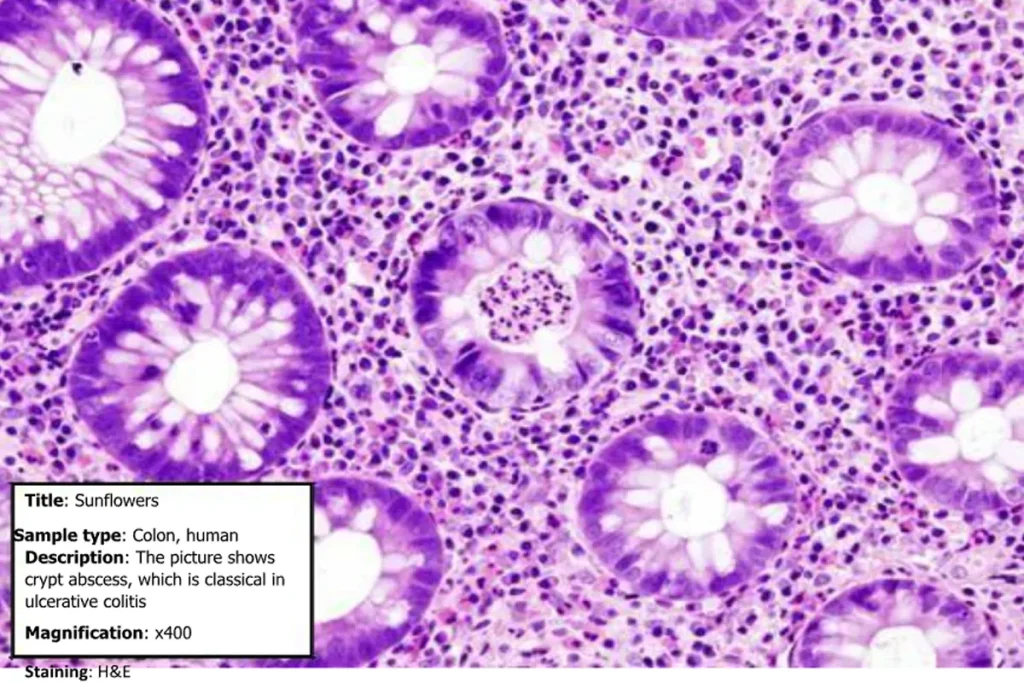

EXAMPLE ENTRY FOR THE BEST MICROGRAPH COMPETITION

- Title (e.g., Sunflowers).

- Sample type (e.g., Intestine, cat).

- Brief description (e.g., The enteritis lesions observed in Infectious Bowel Disease [IBD] patient).

- Magnification/Staining if applicable.